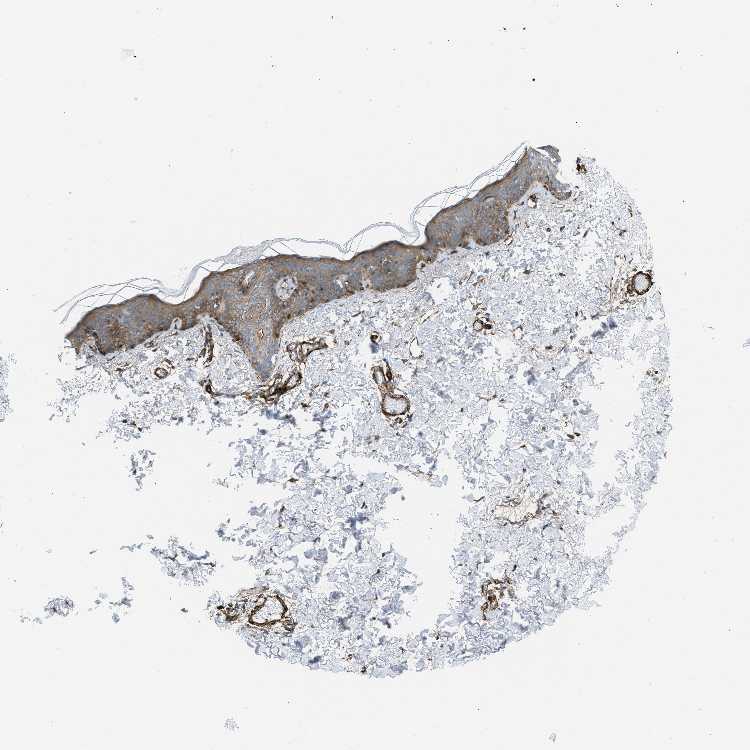

TISSUE PRIMARY DATA SKIN Show tissue menu

SKIN 1 - Antibody stainingi

Antibody staining in the annotated cell types in the current human tissue is reported as not detected, low, medium, or high, based on conventional immunohistochemistry profiling in selected tissues. This score is based on the combination of the staining intensity and fraction of stained cells.

Each image is clickable and will lead to virtual microscopy that enables deeper exploration of all samples and also displays staining intensity scores, fraction scores and subcellular localization as well as patient and tissue information for each sample.

Antibody HPA008066Antibody HPA017330Antibody CAB000006

Langerhans Not detectedMedium-

Arrector pili muscle cells --High

Cells in basal layer --Not detected

Cells in corneal layer --Not detected

Cells in granular layer --Not detected

Cells in spinous layer --Not detected

Endothelial cells --High

Extracellular matrix --Not detected

Fibroblasts Not detectedMedium-

Fibrohistiocytic cells --Not detected

Hair follicles --Not detected

Keratinocytes Not detectedMedium-

Langerhans cells --Not detected

Lymphocytes --Not detected

Melanocytes Not detectedMediumNot detected

Sebaceous glands --Not detected

Vascular mural cells --High